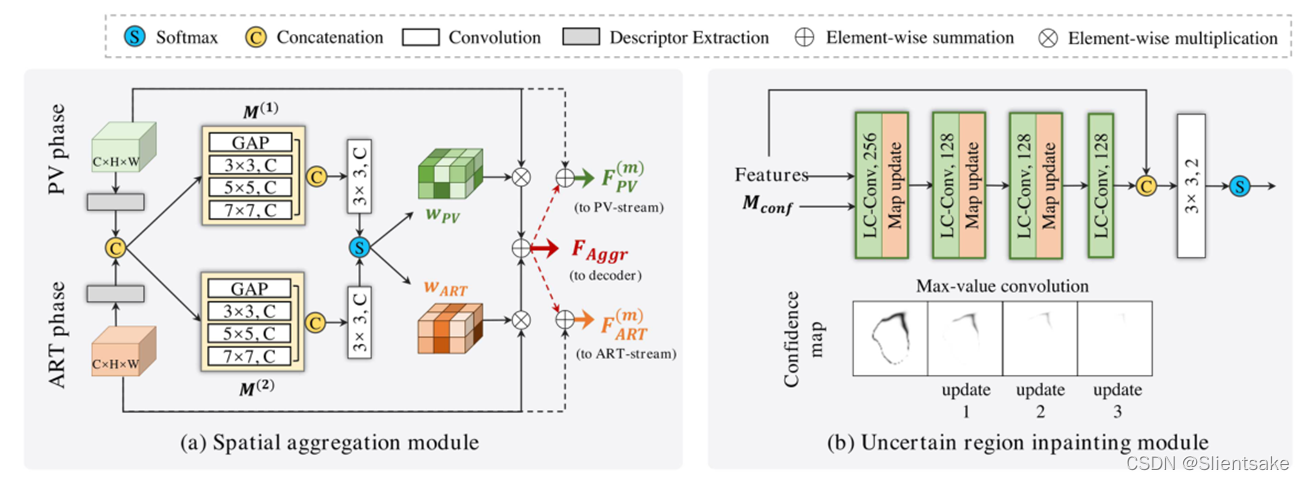

图2(a)示出了具有两个输入特征映射FPV的拟议SAM的详细结构∈ RC×H×W(来自PV流)和FART∈ RC×H×W(来自ART流),SAM模块计算两个像素级响应图,表示为wPV∈ RC×H×W,WART∈ RC×H×W,分别调制FPV和FART。因此,整体跨阶段特征聚合可以表示为:

如何获得合适的响应图是SAM模块的关键。具体而言,SAM模块首先提取输入特征的有效描述符,以减少维数并保留信息特征。为此,对沿通道方向的输入应用平均池和最大池操作。然后,SAM模块学习两个映射函数M(1)和M(2),从特征描述符中建模局部和全局相位间互补关系。具体地说,M(1)和M(2)构建在金字塔卷积结构上(参见图2(a)),即。E采用全局平均池(GAP)层和7×7卷积层提取全局对应;使用两个卷积层(内核大小为3×3和5×5)捕获局部相位间细节。采用M(1)和M(2)的输出得到两个初始响应图w(0)PVA和w(0)ART,通过级联和3×3卷积(注意,在级联之前将间隙层的输出采样到H×W)。通过softmax层对w(0)PVA和w(0)ART进行归一化,从而确保w(c,h,w)PV w(c,h,w)ART=1,从而获得最终响应图。(这部分具体参考原论文)

不确定区域修复模块:

解码阶段采用了四级聚合特征 i∈ 2,3,4,5预测初步概率图。然而,初始结果通常呈现一些模糊和不确定的区域。因此,提出了一个不确定区域修复模块(URIM)来细化模糊区域(尤其是肿瘤边界)。URIM的核心思想是利用具有自信分类分数的像素修复相邻的不确定像素。

置信图计算:

让Si∈ R1×H×W(i∈[1,2])表示初始分段图。Si是属于i类(肝肿瘤或背景)的每个像素p的概率,其中∑2 i=1Si(p)=1。因此,每个像素的分类置信度可以由置信度映射Mconf表示∈ R1×H×W:

其中Smax表示初始贴图中每个像素的最大分数,Smin表示每个像素的最小分数。Mconf 的范围为[0,1],Mconf中的值越大表示置信度越高。(这乱码实在有些严重 有时间再修改一下)

局部置信卷积:

不确定像素通常具有难以区分的特征,因此很难识别其类别。直观地说,如果能让不确定像素从相邻的置信像素中吸收鉴别特征,那么这些不确定像素的分类可能会变得更容易。为此,作者提出了局部置信卷积(LC Conv)运算,其公式如下:

其中X表示当前滑动窗口中的输入特征;x′表示细化特征;Mconf表示像素级置信度图;W表示卷积滤波器的权重,b表示偏差。

比例因子1/sum(Mconf)用于在不同滑动窗口内正则化置信度映射的效果。在每个卷积运算中,LC-Conv强调鉴别特征并抑制不确定特征。利用该机制,相邻窗口中置信度较高的像素对滤波结果的贡献更大,从而使不确定像素接收周围的可分辨特征。在每次LC-Conv操作之后,Mconfis通过3×3最大值卷积层进行更新。

图2(b)显示了URIM模块的详细结构,该模块由四个LC Conv层和3×3内核组成。URIM模块将来自解码器的Mconf和决策特征(softmax层之前的特征映射)作为输入,并产生精确的预测。在细化阶段,不确定像素逐渐吸收更遥远的自信特征,而不确定区域缩小,这与图像修复类似。最后,将细化后的特征和输入特征连接起来,以预测最终结果。

图2:拟议SAM模块(a)和URIM模块(b)的详细结构